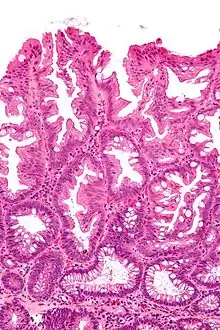

Micrograph of a colorectal villous adenoma. H&E stain

These adenomas may become malignant (cancerous). Villous adenomas have been demonstrated to contain malignant portions in about 15–25% of cases, approaching 40% in those over 4 cm in diameter.[7] Colonic resection may be required for large lesions. These can also lead to secretory diarrhea with large volume liquid stools with few formed elements. They are commonly described as secreting large amounts of mucus, resulting in hypokalaemia in patients. On endoscopy, a "cauliflower' like mass is described due to villi stretching. Being an adenoma, the mass is covered in columnar epithelial cells.